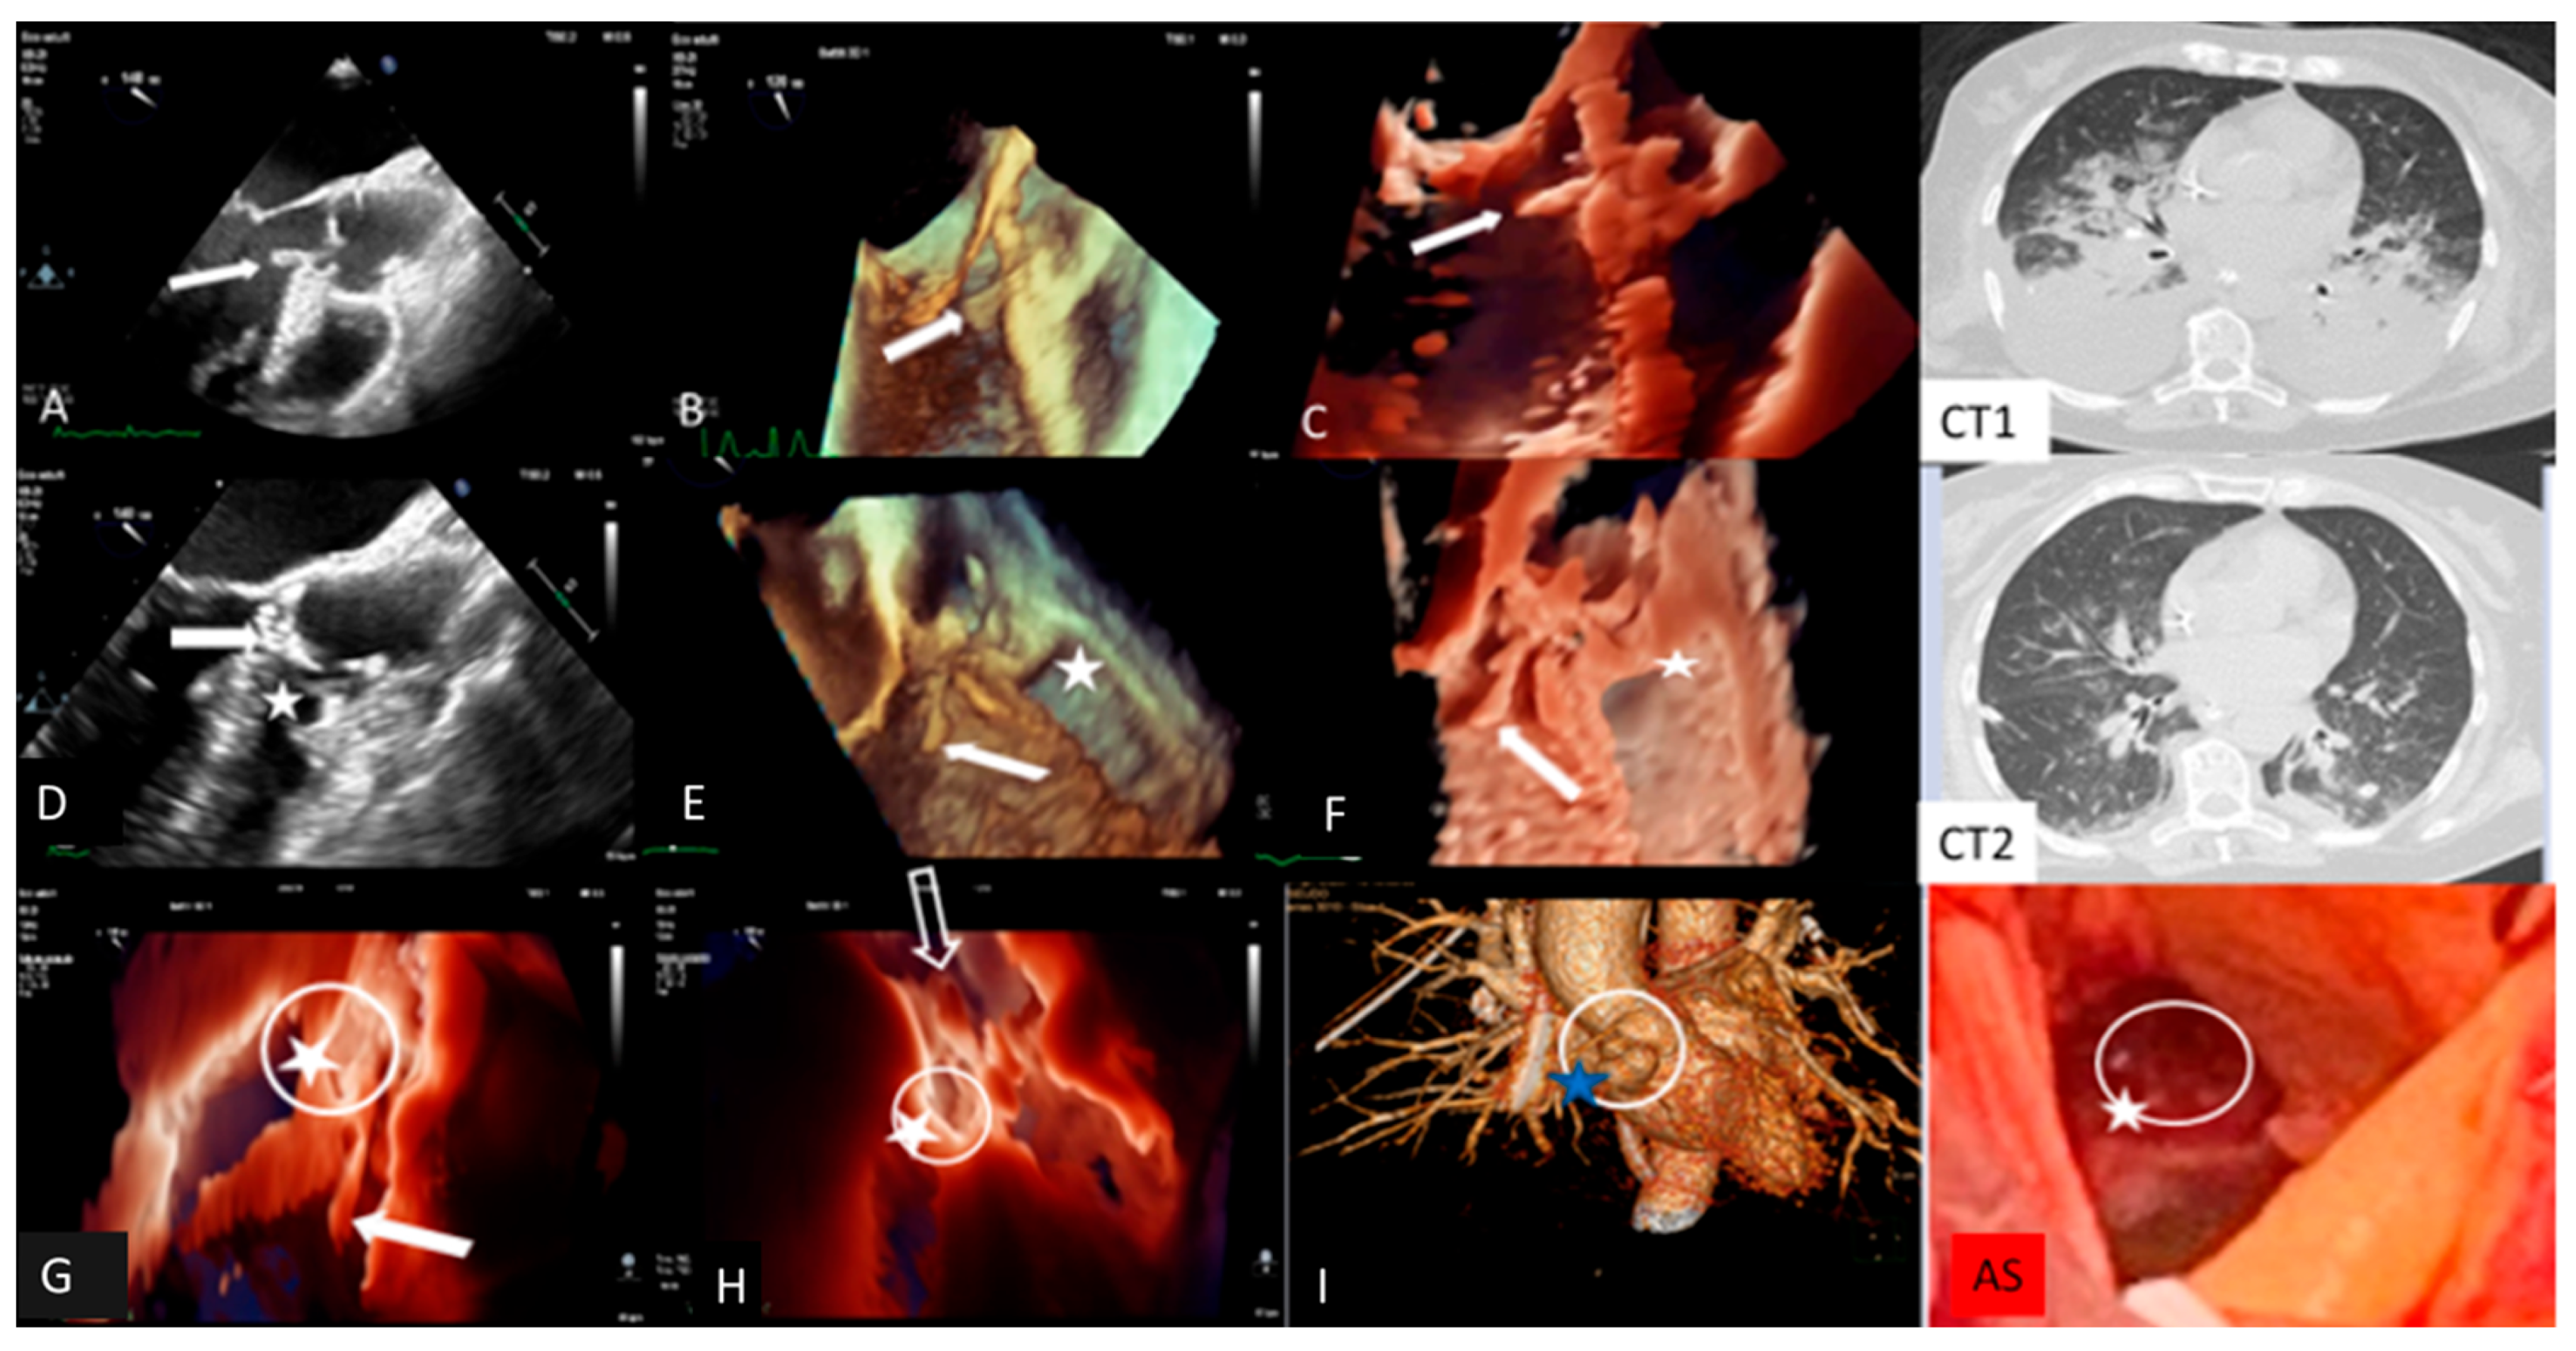

| Clinical Case 5. Streptococcus pneumoniae infection with meningitis, pneumonia, and fulminant endocarditis (“Austrian syndrome”). A 72-year-old female was admitted after 3 days of fever, shortness of breath, and abrupt headache with nausea and vomiting. On admission, the patient appeared confused and troubled. Clinical examination revealed nuchal rigidity without focal neurologic signs. Her temperature was 39 °C, arterial blood pressure 115/60 mm Hg. The clinical diagnosis was initially addressed toward bacterial or viral meningitis vs. COVID-19 with meningoencephalitis phenotype. Lumbar puncture was carried out; cerebrospinal fluid analysis showed hypoglycorrhachia and hyperproteinorrhachia, supporting a diagnosis of probable bacterial meningitis. Empirical antibiotic therapy with intravenous Ceftriaxone, Vancomycin and Dexametasone, was promptly started. A brain CT was negative for intracranial lesions. Baseline and contrast CT showed normal pulmonary findings without parenchymal consolidation or signs of thromboembolism. Pneumococcal antigen in urine was positive and blood culture (BC) showed Gram-positive cocci. Nasopharyngeal Swab (NS) was negative for COVID-19. The final BC result confirms S. pneuomoniae bacteremia, supporting a bacterial meningitis etiology. Targeted antibiotic therapy was introduced, including levofloxacin. After 12 h, the patient showed abrupt cognitive impairment with arterial blood hypotension (80/50 mm Hg) and severe hypoxemia requiring endotracheal intubation. The patient was admitted to the intensive care unit with a diagnosis of pneumococcal meningitis and septic shock. After two days, due to significant clinical improvement, endotracheal intubation was removed. However, during the subsequent two hours the patient showed atrial fibrillation with a high ventricular rate that was reverted with iv amiodarone. Clinical examination revealed a new diastolic regurgitant murmur at cardiac auscultation. Temperature was 37.5°, blood pressure 155/50 mm Hg. Large vegetation with severe AR was shown by TTE. Subsequent TEE confirmed AR due to extensive damage of three valve leaflets with large iso-echogenic (like myocardium echogenicity) vegetation, inserted at the level of the ventricular surface of the right coronary cusps (dimension 20 × 7 mm) and prolapsing in the left ventricular outflow tract. There was moderate MR, pulmonary artery hypertension (sPAP 70 mm Hg), and severe TR. Left ventricular dimension and ejection fraction were normal. A fresh thrombus was found in the left atrial appendage. Inotropic support, with furosemide and heparin infusion, was started. Due to high systemic embolic risk (large aortic valve vegetations and left atrial appendage thrombosis), total body CT was performed. Brain CT was normal, while the thoracic scan revealed bilateral parenchymal consolidation and large pleural effusion with parenchymal edema (Figure 1). Additional NPS and BAL excluded COVID-19. Final diagnosis was “Austrian syndrome” (6), including meningitis, with subsequent pneumoniae and endocarditis due to S. pneumoniae. Although clinically indicated, cardiac surgery was postponed due to the unavailability of an operating room during the COVID-19 outbreak. The next day, hemodynamics remained stable under inotropic, diuretic, and mechanical ventilation support. A new TEE showed unchanged findings, apart from the disappearance of the thrombus in the left atrial appendage. The following day, the patient underwent contrast CT, showing significant improvement of pulmonary findings, a normal coronary anatomy, and double bulging of the aortic root below the coronary artery ostium. Immediate TEE was performed showing, in addition to the previous findings, an intimal tear with a new cavity of the anterior wall of the aortic root at the site of systolic contact of vegetation, suggesting a “kissing” mycotic pseudoaneurysm. In addition, TEE revealed normalization of sPAP and related TR. The patient, due to the added risk of impending root rupture, underwent emergency cardiac surgery. Anatomical inspection confirmed large vegetation and extensive leaflet damage of the tricuspid aortic valve, with a large paravalvular mycotic pseudoaneurysm (Figure 1). The operating strategy involved drainage of purulent material and pseudoaneurysm patch repair, followed by biological valve prosthesis implantation. The leaflet aortic culture was positive for S. Pneumoniae. The postoperative clinical course was uneventful, with complete recovery of the clinical condition. Comment. This case outlines the importance of careful daily clinical examination to target the appropriate pathway for the identification and management of unexpected fulminant IE, which can be superimposed in the deceptive context of meningitis and pneumonia due to S. pneumoniae infection (so-called Austrian syndrome).  |

| Transesophageal echocardiography and computed tomography of fulminant aortic endocarditis. TEE images: (A) two-dimensional; (B) three-dimensional; (C): photorealistic three-dimensional showing large vegetation (arrow) on the aortic valve prolapsing during diastole into LVOT, increasing at 24 h TEE images (D–F) together with an intimal tear communicating with a neocavity (star) on the aortic anterior wall at the site of vegetation contact (dotted arrow), suggesting a mycotic pseudoaneurysm; (I): three-dimensional computed tomography showing double bulging of the anterior aortic wall (dotted circle) overlapping photorealistic 3D images (G,H) and surgical specimen findings (AS). Computed tomography showing bilateral pulmonary parenchymal consolidation and large pleural effusion (CT1), which improved following thoracentesis and intensive medical therapy (CT2). |